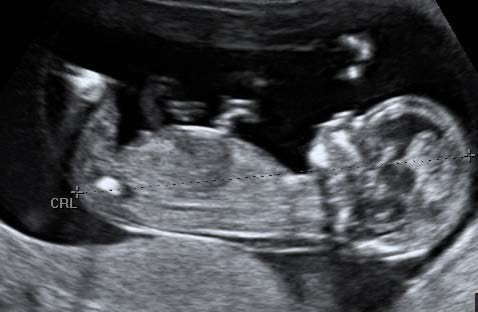

Where both dating and 1st trimester screening are requested and the CRL is between 45.0 and 84.0mm, the pregnancy should be dated using the CRL measurement.

Criteria for measurement of the fetal crown rump length (CRL) as part of the combined 1st trimester screening programme

The CRL range should be between 45.0 and 84.0 mm.

The magnification of the fetus should be as large as possible clearly demonstrating the entire crown-rump length.

A midline sagittal section of the whole fetus should be obtained with the fetus horizontal on the screen, either supine or prone. The fetus should be in a neutral position with fluid visible between the fetal chin and chest, neither hyper extended nor flexed.

The best of three measurements should be taken. Linear callipers should be used to measure the maximum un-flexed length. Intersection of the callipers (+) should be placed on the outer margin of the skin borders of the CRL. Two images of the measured CRL must be retained, one for the patient record and one for audit purposes.